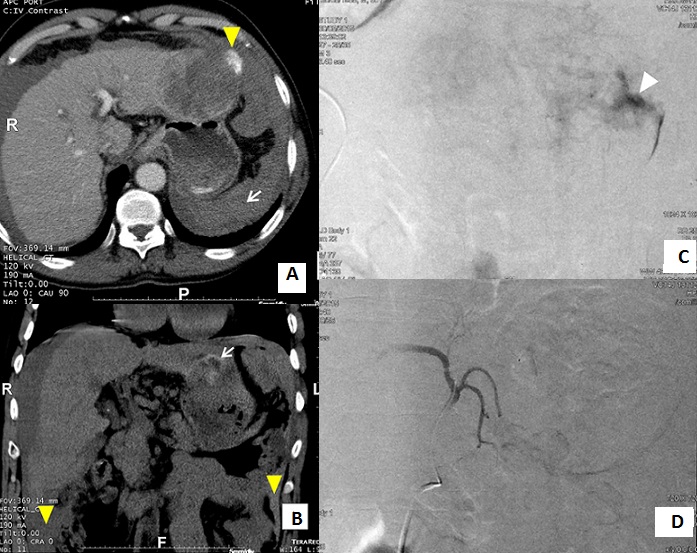

La rupture spontanée de carcinome hépatocellulaire (CHC) représente une complication relativement rare et potentiellement fatale. Les situations cliniques sont différentes depuis l'hémorragie compensée jusqu'à la rupture péritonéale massive entraînant un hémopéritoine abondant mettant en jeu le pronostic vital. Le diagnostic repose sur le scanner qui détecte la tumeur et l'éventuelle extravasation si le saignement est actif. La mise en évidence de l'extravasation se fait parfois au temps artériel, mais elle est presque toujours visible au temps portal. L'embolisation est le premier traitement en urgence à envisager dans la rupture de CHC ce qui ne préjuge pas d'une autre prise en charge ultérieure en cas d'évolution favorable. Avec un taux de succès dépassant 90%, il s'agit d'une méthode peu invasive en comparaison avec la chirurgie. On peut effectuer soit une embolisation simple, soit d'emblée une chimio-embolisation lipiodolée. Nous rapportons l'observation d'un patient âgé de 60 ans chez qui a été découvert il y a un mois un CHC de 7 cm du foie gauche sur foie cirrhotique. Il avait présenté cinq heures avant sa consultation une épigastralgie brutale et intense associée à une distension abdominale, un retentissement hémodynamique et une déglobulisation (Hb:7,5 g/dl). Le scanner abdominal (A, B) a montré un CHC du foie gauche compliqué d'hémorragie intrapéritonéale de moyenne abondance avec une extravasation du produit de contraste en flaque péritumorale. Après transfusion sanguine et stabilisation de son état hémodynamique, il lui a été réalisé une chimio-embolisation (C, D) permettant de contrôler le saignement. Les suites immédiates étaient favorables.